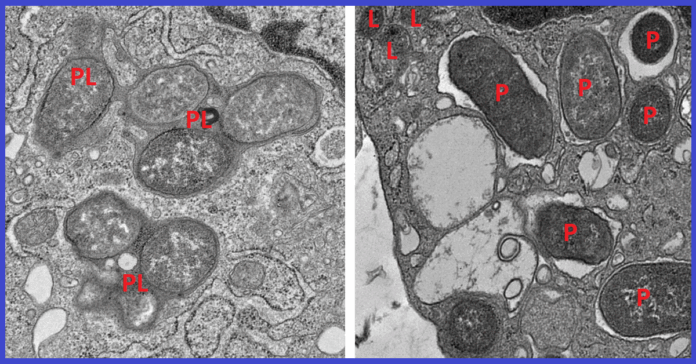

Recent research sheds light on the complex relationship between NOD2 and girdin in Crohn’s disease, using innovative AI technology. Key insights include:

- Importance of Girdin: Mice lacking girdin exhibited gut microbiome imbalances and severe inflammation, leading to increased mortality from sepsis.

- AI Integration: By employing AI, researchers effectively classified and tracked immune system interactions, clarifying longstanding debates surrounding Crohn’s disease.